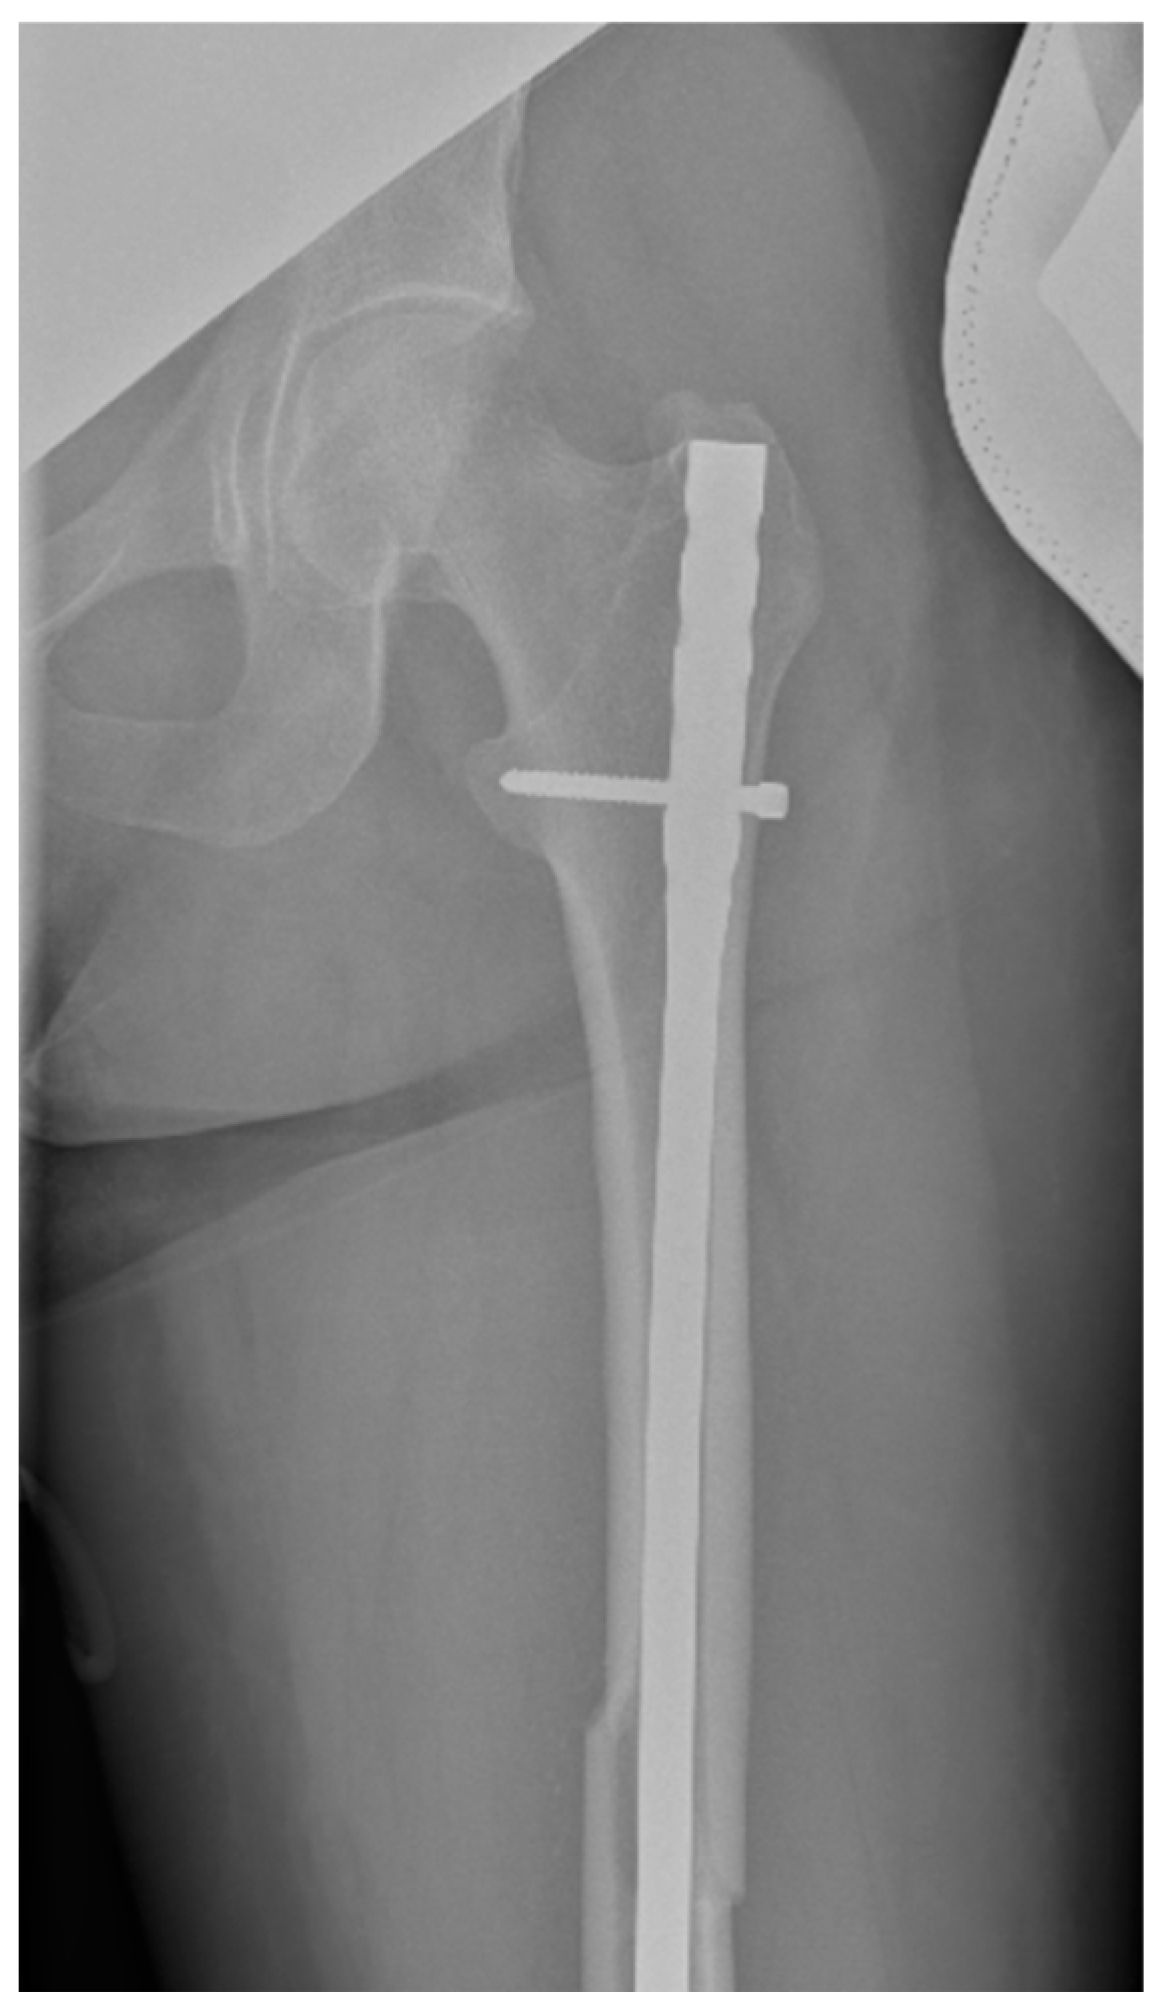

Surgical intervention was performed by a multidisciplinary team: an anesthetist, an obstetrician, a neonatologist, and an orthopedist. She underwent spinal anesthesia utilizing 0.5% bupivacaine, with the extraction of a healthy female baby, weighing 3200 g, with an Apgar score of 9 by C-section and bilateral tubal ligation at the request of the patient, followed by a successful fracture repair under intraoperative C-arm fluoroscopy. The surgical intervention for the fracture of the femur consisted of closed reduction and osteosynthesis with an anterograde intramedullary nail locked proximally and distally with a screw. The postoperative X-ray control revealed good fracture reduction and correct placement of the osteosynthesis material (Figure 2 and Figure 3).

Figure 2.

Postoperative anteroposterior view of the left thigh—proximal pole of the intramedullary anterograde nail fixed with one screw.